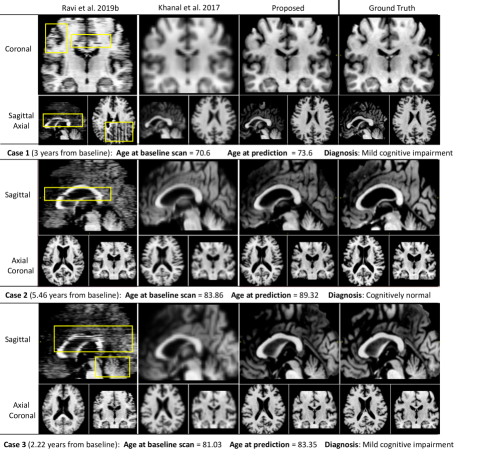

5.1 Qualitative Comparison Study

Here we compare our framework to the two state-of-the-art solutions available for MRI synthesis: i) the baseline DANI-Net obtained by independent training (and stacking) of 2D slice models [38]; and ii) the biomechanical approach proposed in [20], which required down-sampling of the MRI resolution (by a factor of 2) for computationally feasible training times, followed by re-scaling to the original resolution using bilinear interpolation.

Figure 5 shows that our approach provides the best results: fewer artefacts and superior resolution (less smoothing). Notably, images generated by [20] show excessive smoothing, whereas images generated by [38] contain notable artefacts.

For completeness, Fig. 1 shows an example of an entire simulation obtained using the full configuration of 4D-DANI-Net. Expected neurodegeneration is apparent in the sequence, including ventricular expansion, hippocampus contraction, and cortical thinning.